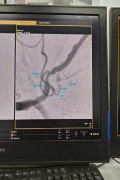

С 26 августа заведующий кабинетом ангиографии Руцкий Сергей Викторович проходил обучение на базе отделений ангиохирургии и эндоваскулярной хирургии АО «Национальный научный центр хирургии им. А.Н. Сызганова» в городе Алматы.

Сергей Викторович усовершенствовал навыки различных видов эндоваскулярных эмболизаций: легочных, маточных и других периферических артерий, химиоэмболизации артерий печени, а также стентирование коронарных, сонных и других периферических сосудов. Кроме того овладел навыками лечения и ведения пациентов с врожденными ангиодисплазиями, артериовенозными мальформациями и гемангиомами у взрослых и детей.